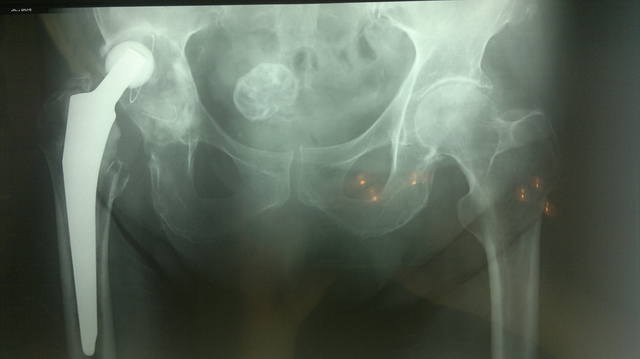

Здравствуйте, дорогие читатели нашего форума!<br /><br />Эндопротезирование при дегенеративно-дистрофических заболеваниях, а также травмах и их последствиях остается актуальным, бурно развивающимся направлением в современной ортопедии. С каждым годом в мире увеличивается число лиц нуждающихся в выполнении подобного рода операций. <br /><br />Замена собственного сустава искусственным позволяет огромной категории больных избавиться от хронического болевого синдрома, восстановить объем движений и функцию пораженного сустава, вернуться к своей профессиональной деятельности. <br /><br />В то же время известно, что каждый эндопротез имеет свой определенный "срок службы", длительность которого зависит от целого ряда обстоятельств. С одной стороны  это качество материалов, применяемых для изготовления имплантатов, с другой - особенности пациента и т.д.<br /><br />С увеличением пула пациентов, которым была выполнена первичная операция, возрастает нуждаемость  в так называемом "ревизионном эндопротезировании". Актуальность темы обусловлена тем, что хирург сталкивается при ревизии с уже не обычной ситуацией, в которой анатомические ориентиры часто бывают разрушены.<br /><br />В тему предлагаю выкладывать реальные клинические случаи и примеры ситуаций, с которыми сталкивается ортопед при ревизионном эндопротезировании.<br /><br />Начну с двух случаев. <br /><br />Первый: женщина, 80 лет, срок службы тотального цементного эндопротеза тазобедренного сустава 19 лет.<br /><br /> <br /><br /> <br /><br />Второй:<br /><br />женщина, 64 года, тотальный безцементный эндопротез тазобедренного сустава, срок службы 15 лет:<br /><br /> <br /><br />Третий:<br /><br />женщина, 60 лет, тотальный цементный протез тазобедренного сустава, срок службы 10 лет:<br /><br />